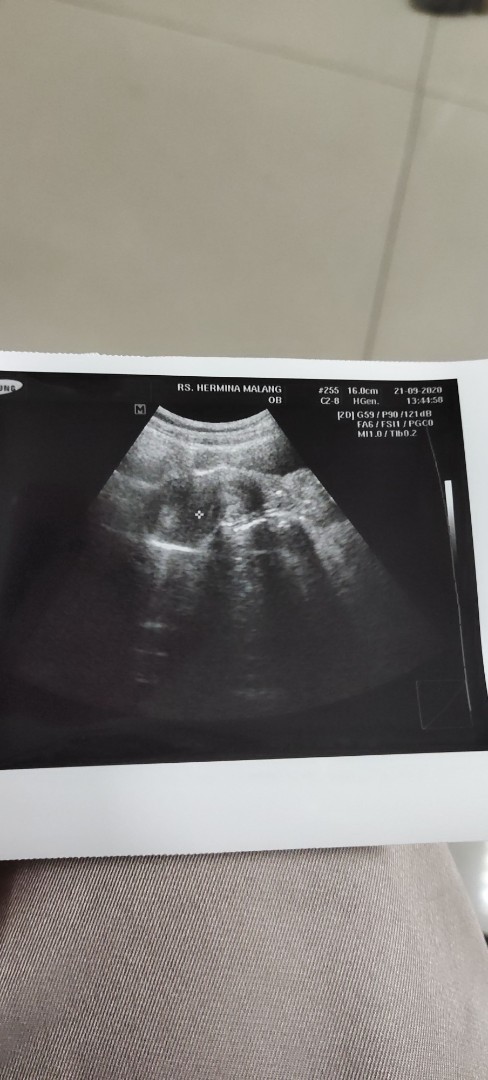

ini hasil USG sy.. kata dokter sy hamil 2 Minggu menurut bunda2 apa KH benar ini kantong janin?

kalo kata dokternya gmna sy usg 2w baru gumpalan darah